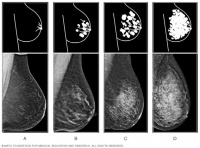

乳腺癌筛查新争议:密度过高,该告知吗?